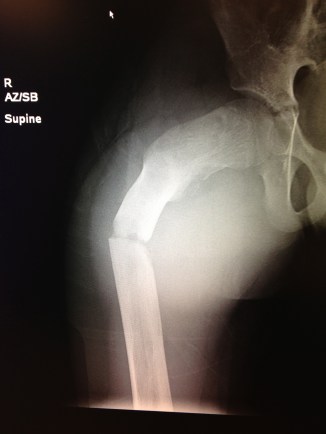

If you’re not into reading X-rays, let me explain it to you: see that big crack in the femur? Yeah, that shouldn’t be there.

Two weeks ago my son Bobby (10 years old) was playing basketball. He fell backwards and everyone heard a loud CRACK! If you think that’s an unusual way to break a femur, it is. The doctors have diagnosed him with “fibrus dysplasia,” a weakening of the bone. That makes his already difficult recovery longer, and perhaps means he will need future surgeries to “augment” the bone.